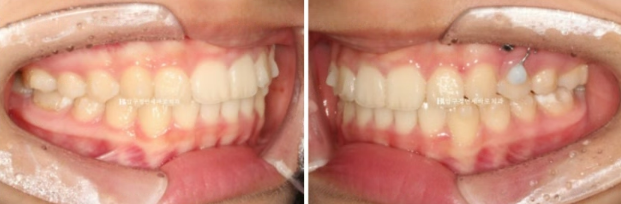

오른쪽 교합은 나쁘지 않습니다.

23.08

왼쪽은 3급 교합관계 때문에 왼쪽 어금니는 잘 안 물리고 이것이 앞니에 영향을 주어 위 앞니 중심이 인중과 얼굴에 비하여 틀어져 있습니다.